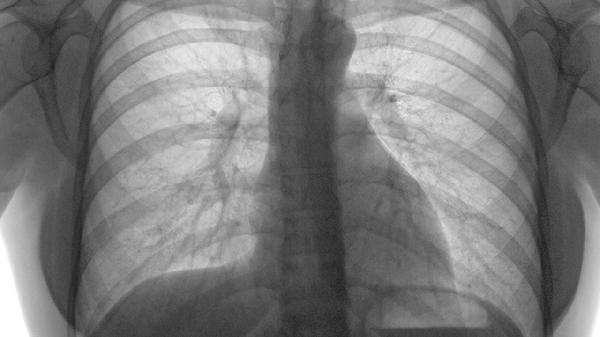

胸部肿瘤放疗后出现放射性肺炎导致干咳时,中医辨证属气阴两虚者可配合使用。需定期复查CT,避免与放疗同期使用吉非替尼片等靶向药。